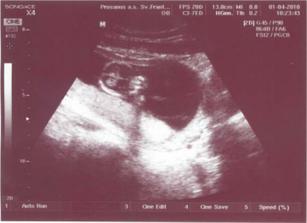

# 1.4. o 9.30 - dnes som si chvíľku počkala, než som sa dostala do ordinácie... Ale aby mi ten čas rýchlejsie ušiel, poslala ma sestrička na odber na AFP :( A tej krvičke sa zase vôbec nechcelo! Pani doktorka robila UTZ prvýkrát cez bruško, len malé sa nechcelo dať zmerať 🙂 Napokon sa na chvíľočku otočilo bokom a prezradilo svoje miery: 76mm. Podla kalendára by sme mali byť presne v 14tt, ale podľa veľkosti 13+5. Moj krvný tlak bol nižší, len 100/70, ale možno to bude tým, ze tento týžden bol náročný a chodili sme neskoro spávať... Ale aj málo pijem, viem, no ešte som nenašla vodu, ktorá by mi vyhovovala (a nepýtala sa naspäť). Bábo sa má zatiaľ výborne, tak sa pokúsim to pitie zlepšiť, aby mu bolo ešte lepšie 🙂